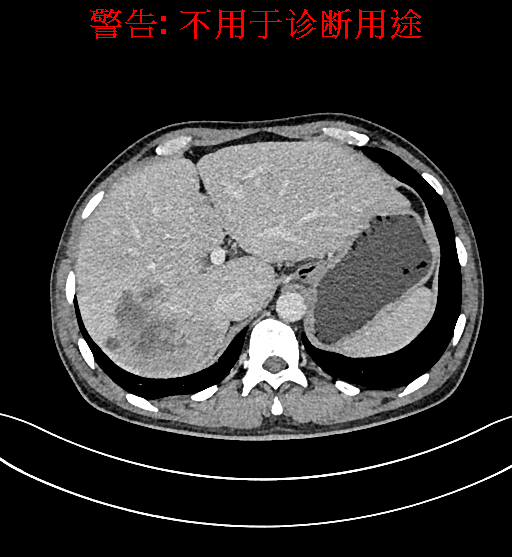

上腹部增强CT示肝右叶多发低密度结节、片团影伴肝门区、肝胃间隙多发肿大淋巴结,原发性肝Ca可能性大,请结合临床肝硬化肝脏小囊肿。

术前CT检查:

静脉期